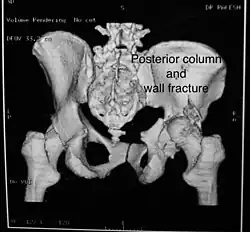

Posterior column and wall fracture as seen on 3D CT -

Posterior column and wall fixed using screws and plates

| Posterior column | As with posterior wall injury, this also typically occurs due to dash board injury. | Posterior column + Posterior wall | These fractures are extensions of elementary fractures. With the involvement of the posterior wall, the difficulty in treatment increases. These fractures are rarely amenable to non-surgical treatment. Due to posterior wall fracture, the hip is usually dislocated posteriorly, requiring immediate reduction of dislocation and surgical reconstruction after a few days.

The posterior column with posterior wall fracture occurs due to dashboard injury. The anteroposterior view may give clues to these injuries. Judet views and CT scans help in knowing the extent of the injury. |